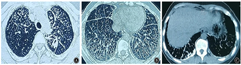

患者女,35岁,因"体检发现肺部病灶8年,咯血半个月"于2022年9月9日入院。患者8年前体检行胸部CT检查发现双肺弥漫结节影(图1);2014年10月28日在当地医院完善气管镜检查、肺功能检查,均未见明显异常;后行肺穿刺术,术后病理为大部分血块、皮肤纤维、横纹肌细胞,见少量钙化。未予以治疗。2022年8月20日患者在家中突发咯血1次,量约10 ml,颜色鲜红,后未再出现咯血。2022年9月3日患者查胸部CT提示双肺弥漫性病变,双侧胸膜增厚伴钙化,左上肺结节伴空洞(图2)。左上肺结节及空洞为新发病灶。为进一步诊治,于2022年9月9日收住南京中医药大学附属南京医院结核科。既往史:患者既往身体健康,否认结核病史,否认高血压、心脏病、糖尿病、脑血管病及精神疾病,从事足浴店服务员工作,否认粉尘接触史,否认有疫水、疫源接触史,否认冶游史,否认吸烟、饮酒史,否认食物、药物过敏史,家族中姐姐曾体检发现双肺弥漫性病灶,未进一步检查,父母为表兄妹近亲结婚。入院体检:体温36.4 ℃,心率80次/min,呼吸18次/min,血压124/85 mmHg(1 mmHg=0.133 kPa)。患者意识清楚,精神良好,口唇无发绀,浅表淋巴结未触及肿大,双肺呼吸音清,未闻及干湿性啰音,四肢关节无异常,无杵状指,体格检查未见其他异常。实验室检查:血尿粪常规、血生化、凝血功能、自身抗体、血沉、血肿瘤标志物、血清血管紧张素转化酶均正常;血抗结核抗体阴性,血清γ-干扰素释放试验阳性,结核菌素试验强阳性;3次痰涂片找抗酸杆菌阴性,痰普通菌、真菌培养阴性,痰脱落细胞检查未找到肿瘤细胞。入院诊断为"继发性肺结核,双肺弥漫性病灶待查"。患者除咯血外,无明显其他症状,入院后完善甲状腺超声、泌尿系彩色超声、腹部CT,均未见明显异常,心脏彩色超声提示心内结构未见明显异常,左室收缩功能正常范围。为明确诊断,行支气管镜检查,术中可见左肺上叶后段开口轻度狭窄,黏膜粗糙水肿,于此处用60 ml生理盐水冲洗,留取灌洗液送检,左肺下叶基底段见色素沉着,开口未见明显狭窄,右肺上叶可见色素沉着,见可疑黑色丝状物,予以吸出。灌洗液涂片找抗酸杆菌阴性,灌洗液结核分枝杆菌DNA<500 copies/ml,灌洗液送检GeneXpert MTB/RIF结核分枝杆菌检测阳性,灌洗液送检结核分枝杆菌靶向高通量基因测序检测出结核分枝杆菌复合群,序列数为18。肺结核诊断成立。考虑到患者父母有近亲结婚家族史,姐姐有类似肺部病灶,影像表现为双肺弥漫性病变和胸膜下多发钙化灶,后行外周血基因分析(表1)检查,提示SLC34A2基因11号外显子纯合子突变(c.1267G>A)。综合分析,患者影像表现为双肺弥漫病灶伴胸膜下片状钙化,左上肺结节伴空洞。结合患者家族史、住院期间相关检查结果以及基因分析结果,考虑诊断为"PAM合并肺结核"。给予异烟肼、利福平、吡嗪酰胺、乙胺丁醇抗结核治疗,定期随访。1个月后复查胸部CT(图3)提示左上肺病灶较前略吸收,其余病灶未见明显改变。

PAM因为症状不典型,在诊断时多依靠影像学检查,同时结合肺活检病理及相关家族史。临床上也可以进行分子遗传学检查来进行诊断。本例患者有明确的家族史,其父母为表兄妹近亲结婚,姐姐体检时也发现双肺弥漫病灶。患者8年前的影像表现为双肺弥漫性病变,可见"火焰征",即胸膜下多发片状钙化影,符合PAM影像表现。肺穿刺病理结果可见部分钙化,符合PAM的病理学改变。分子遗传学检查提示SLC34A2基因11号外显子纯合子突变,单纯该基因型突变导致PAM为首次在亚洲人群中发现,既往有国外文献报道过第11外显子突变引起PAM的案例[12];在国内案例报道中,也有第8个外显纯合子突变合并第11个外显子突变的案例,突变位点均为1267G>A(P.Gly423Arg),并且在本案例中通过蛋白功能预测软件分析提示该位点为有害突变。因此,高度怀疑此突变与PAM发病相关。考虑PAM可能性大。同时,患者肺泡灌洗液GeneXpert MTB/RIF结核分枝杆菌检测阳性,该项检查对结核分枝杆菌感染的敏感度高于涂片及培养,特异度可达98%~100%[13]。临床中可以通过Genexpert MTB/RIF与涂片或胸部CT检查结合,用于诊断疑似的肺结核患者。根据我国《结核病病原学分子诊断专家共识》[14],当分子生物学检测结果阳性、细菌学检测阴性时,应以分子生物学检测结果为准,视为结核分枝杆菌阳性。同时灌洗液送检结核分枝杆菌靶向高通量基因测序提示检测出结核分枝杆菌复合群,序列数为18,进一步证实了肺结核诊断。经过抗结核治疗后,患者左上肺病灶较前吸收,综合考虑判断该患者为PAM合并肺结核。不过在本案例中,患者父母有近亲结婚史,姐姐有类似胸部影像表现,但未能获得患者父母及姐姐的相关临床资料,无法确定其家系SLC34A2基因的遗传特征。本例报道的SLC34A2基因11号外显子纯合子突变(c.1267G>A)为首次在亚洲人发现的第11外显子的核苷酸突变,通过蛋白功能预测软件REVEL预测为有害突变,高度怀疑此突变与PAM发病相关,但仍需进一步研究证实。

PAM在胸部CT上主要表现为稀薄化的弥漫性磨玻璃影、密度较高的粟粒状结节、胸膜下小结节、胸膜下线性钙化("白描征")、胸膜下片状钙化影("火焰征")、结节性钙化、沿小叶间隔的钙化等[15]。在临床上需要与尘肺、血行播散型肺结核、结节病、肺泡蛋白沉积症等疾病鉴别。急性血行播散型肺结核CT影像表现为两肺广泛均匀分布粟粒大小的结节状密度增高影,特点为"三均匀",即病灶分布均匀、大小均匀和密度均匀。而亚急性血行播散型肺结核"三均匀"特征不明显,可表现为新旧病灶共存,可夹杂斑片状、结节状阴影,可伴坏死和空洞。PAM虽然也可以表现为双肺多发粟粒状结节影,但往往结节密度高,分布不均匀,往往伴有自上而下增多的特点,多伴有胸膜下钙化[16]。在本例中,患者胸部CT除双肺弥漫结节影外同时合并左肺上叶尖后段实性结节影,可见空泡及毛刺,除考虑肺结核外,还需要同肺癌、肺脓肿、肺放线菌病、血管炎、肺梗死等疾病相鉴别。肺结核引起的空洞型病灶以薄壁多见,周围常有卫星灶,可伴粗长毛刺或受纤维牵拉而导致空洞形态不规则,肺癌引起的空洞一般为厚壁,内缘凹凸不平,有壁结节,肿块周围伴有毛刺。上述疾病在影像表现上具有相似之处。当仅凭影像学无法确诊时,需要依赖病原学、病理学、免疫学等相关检查加以鉴别。

PAM是一种罕见疾病,合并肺结核的病例则更为罕见,PAM早期症状不明显,病程长,大多仅仅表现为影像学改变,单纯PAM多为偶然体检中发现[17],而合并肺结核的患者则可在早期即出现发热、盗汗、咳嗽、乏力、呼吸困难等症状。在影像学上,PAM合并肺结核的患者胸部CT除表现为双肺弥漫结节影外,还可伴有"树芽征"、斑片结节影、空洞等表现[18]。根据已有报道提示,大部分PAM合并肺结核的患者往往是在诊治肺结核的过程中偶然发现PAM[5],而造成漏诊误诊的主要原因可能是缺乏对PAM的认识,诊断思维局限,没有进行特异性的医学检查[19]。PAM与肺结核之间目前认为仅存在偶然的联系,但通过对此类疾病的探讨,认识到在诊治常见病及多发病的过程中,需要拓宽视野,提高对少见疾病的认识,及时发现合并罕见疾病的情况。